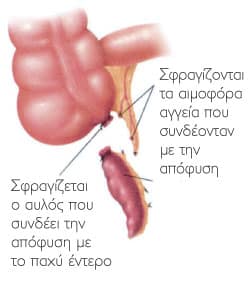

Η λαπαροσκοπική σκωληκοειδεκτομή εκτελείται με τη χρήση λαπαροσκοπικών εργαλείων, επιτρέποντας τη διεξαγωγή της επέμβασης μέσω τριών μικρών τομών στο κοιλιακό τοίχωμα, συνήθως κάτω από τον ομφαλό, στο δεξιό λαγόνιο βόθρο και στην υπερηβική περιοχή.

- Ανίχνευση της σκωληκοειδούς απόφυσης: Η σκωληκοειδής απόφυση ανιχνεύεται και ανυψώνεται με τη βοήθεια λαπαροσκοπικών εργαλείων. Στη συνέχεια απολινώνεται στη βάση της, αποκόπτεται και αφαιρείται.

- Κλείσιμο των τομών: Μετά την αφαίρεση της σκωληκοειδούς, οι μικρές τομές ράβονται ή σφραγίζονται με ειδική χειρουργική κόλλα.